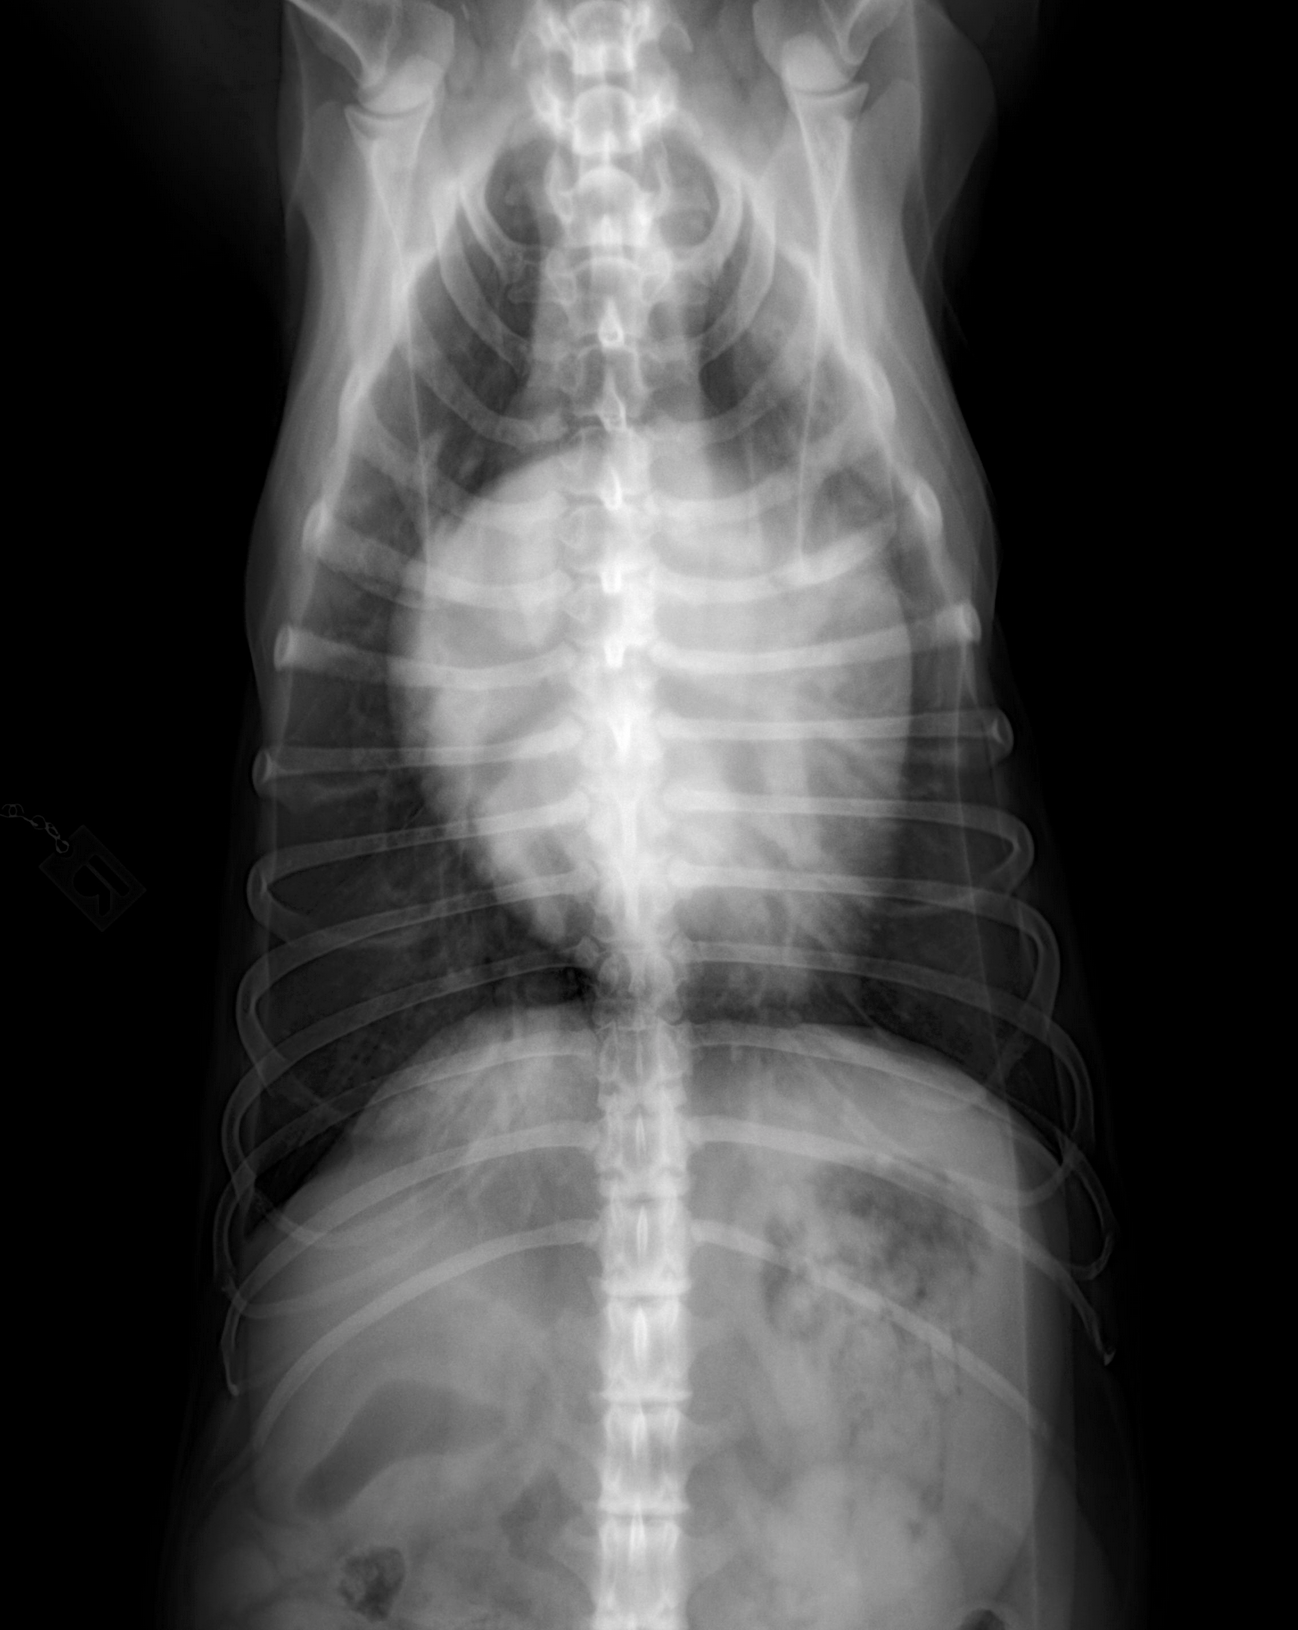

Auf den Röntgenbildern bestätigt sich das, was bei der Untersuchung schon verdächtig war: Das Herz ist deutlich zu groß und man kann ein Lungenödem, also gestaute Gefäße sowie Wasser in der Lunge erkennen.